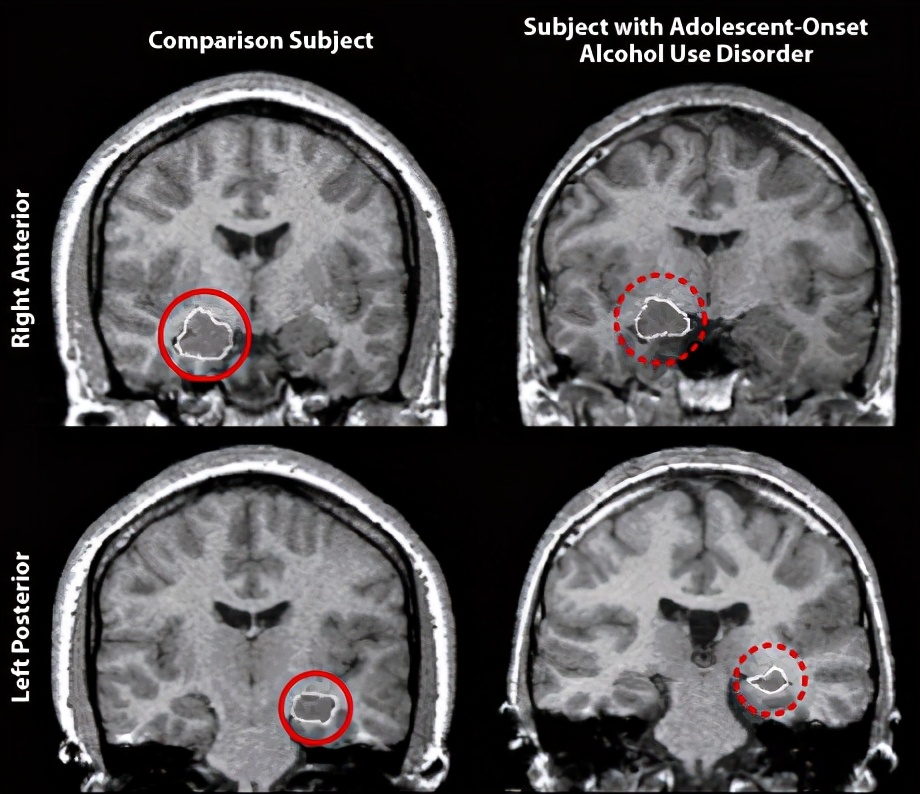

上图显示的是一个健康人(左侧上下2图)和一个青少年时期就开始饮酒的酒精成瘾者(右侧上下2图)的脑核磁成像,上排2个图像特意圈出右侧海马,下排2个图像特意圈出左侧海马。可以发现,右侧酒精成瘾者的大脑体积明显小于对照,左右海马都发生了明显萎缩。